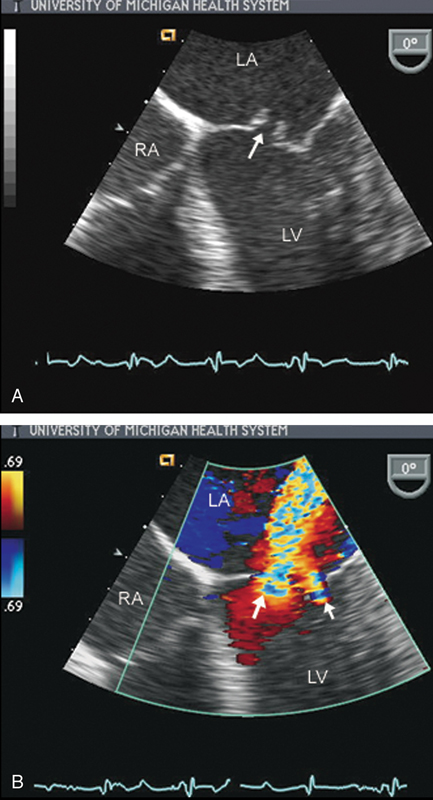

فحوصات تشخيصية لبعض امراض القلب والشرايين التاجية